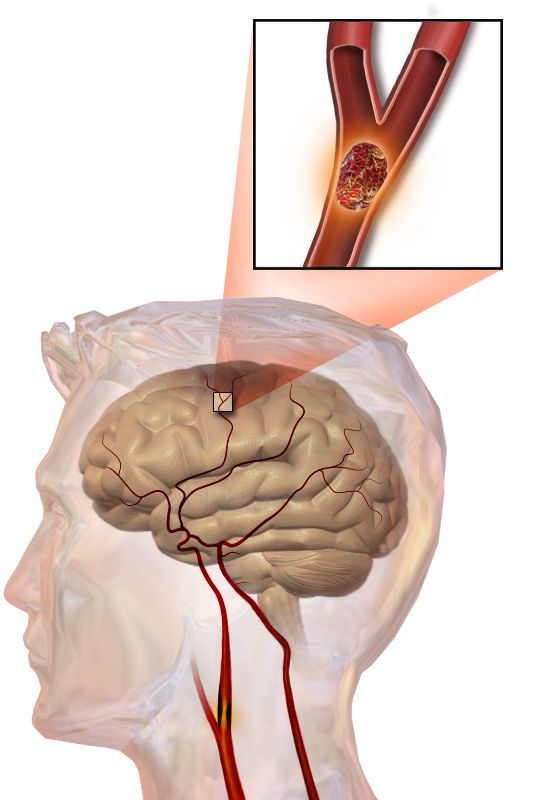

Infart cerebral accident vascular cerebral

Un accident vascular cerebral (AVC) o accident cerebrovascular, vessament cerebral o ictus cerebral és un episodi agut d’afectació de la circulació cerebral; es produeix una lesió irreversible en un territori cerebral a causa de la pèrdua de flux sanguini al cervell, que produeix una sèrie de símptomes i/o signes variables en funció de l’àrea cerebral afectada. Els accidents cerebrovasculars o ictus (trombosi o vessament cerebral, antigament anomenat apoplexia) són causats per un trastorn de la circulació cerebral, que ocasiona una alteració transitòria o definitiva del funcionament d’una o diverses parts de l’encèfal (vegeu la figura).

“Ictus” és el nom científic d’allò que vulgarment és conegut amb diferents expressions: feridura, apoplexia, vessament cerebral, embòlia cerebral trombosi i d’altres. Cada ictus és diferent i la gent que el pateix està afectada de formes diferents; comunament, els classifiquem entre ictus isquèmic i ictus hemorràgic.

Hi ha dues grans categories d’AVC: ictus isquèmic i ictus hemorràgic. En qualsevol dels dos casos, el flux sanguini del cervell resta interromput, es produeix una isquèmia cerebral i les cèl·lules cerebrals moren per manca d’oxigen.

L’ictus isquèmic és el més freqüent (entre un 80-85% dels ictus) i es produeix per l’oclusió d’una artèria cerebral; això provoca una disminució del flux sanguini de l’àrea irrigada per l’artèria i, per tant, una lesió parcial o total del parènquima cerebral corresponent.

Les dues causes més habituals d’ictus isquèmic són:

- Coàgul de sang: un coàgul o trombe es pot formar a una artèria o bé originar-se en el cor en el cas que hi hagi alteracions cardíaques com comunicacions anòmales entre cavitats i/o alteracions del seu ritme. També poden arribar coàguls d’altres llocs de l’organisme fins al cor, i d’allà estant ser enviats cap a la circulació cerebral.

- Ateroma: lesions focals que s’originen a la capa interna (endoteli) de les artèries per acumulació de lipoproteïnes de baixa densitat (LDL) que circulen pel torrent sanguini i s’incrusten a la paret de l’artèria.